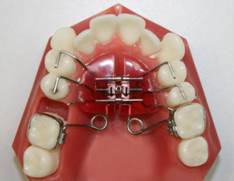

Tedavi Yöntemleri Self-Ligating Sistemler Gölcük Ortodonti Lingual Ortodonti Fonksiyonel Aparey eCligner Sistemi Ağız Dışı Apareyler Hareketli Apareyler Gömülü Kanin Dişi Tedavisi